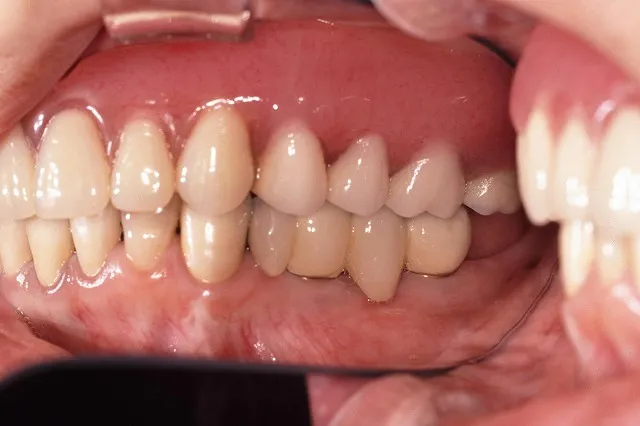

■治療前